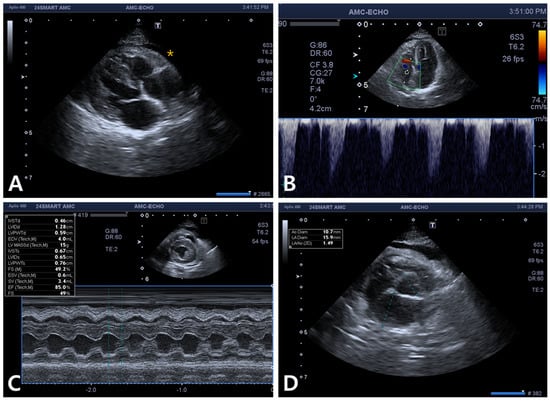

2. Case Description